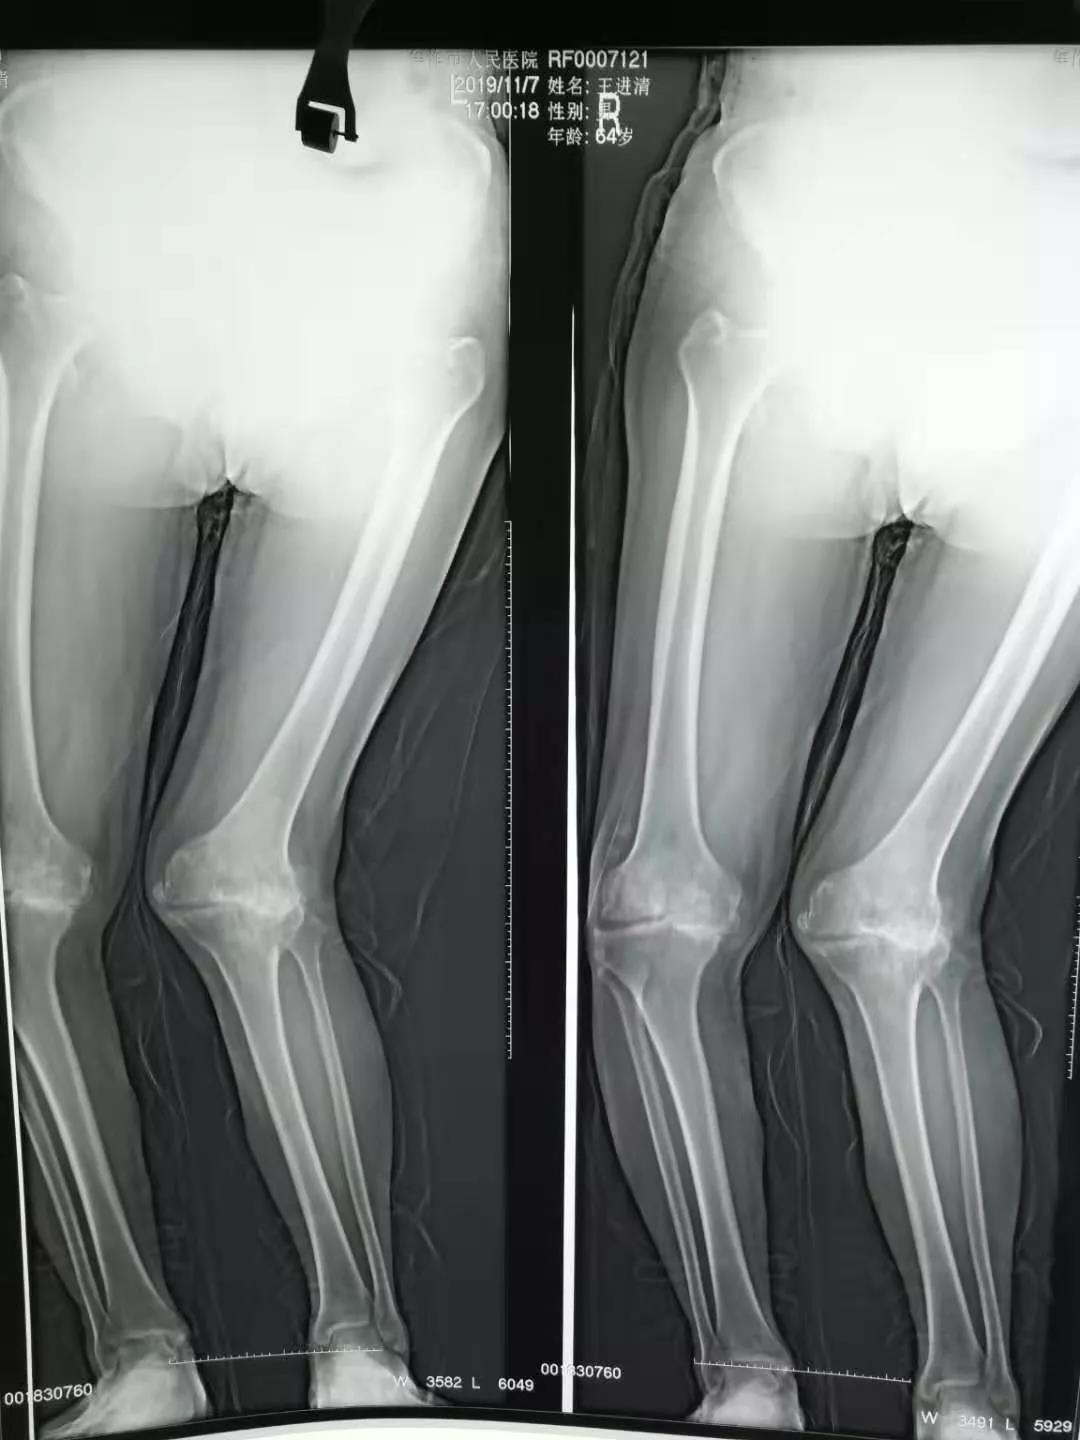

关节外科主任吴若丹和主治医师姚鹏举接诊后,组织了科内会诊:王先生病程己二十余年,右膝内翻膨大畸形,左膝外翻膨大畸形,膝关节活动度明显减小。结合双膝关节X线片检查,患者双膝关节骨质增生明显,内外侧关节间隙消失,左膝关节胫骨平台骨缺损,关节半脱位。吴若丹主任总结后认为:考虑患者自身体质及手术难度,治疗方案为手术分两次进行,第一次行右膝关节内翻畸形关节置换,使用普通假体。第二次行左膝关节外翻畸形关节置换。行acck假体置换。